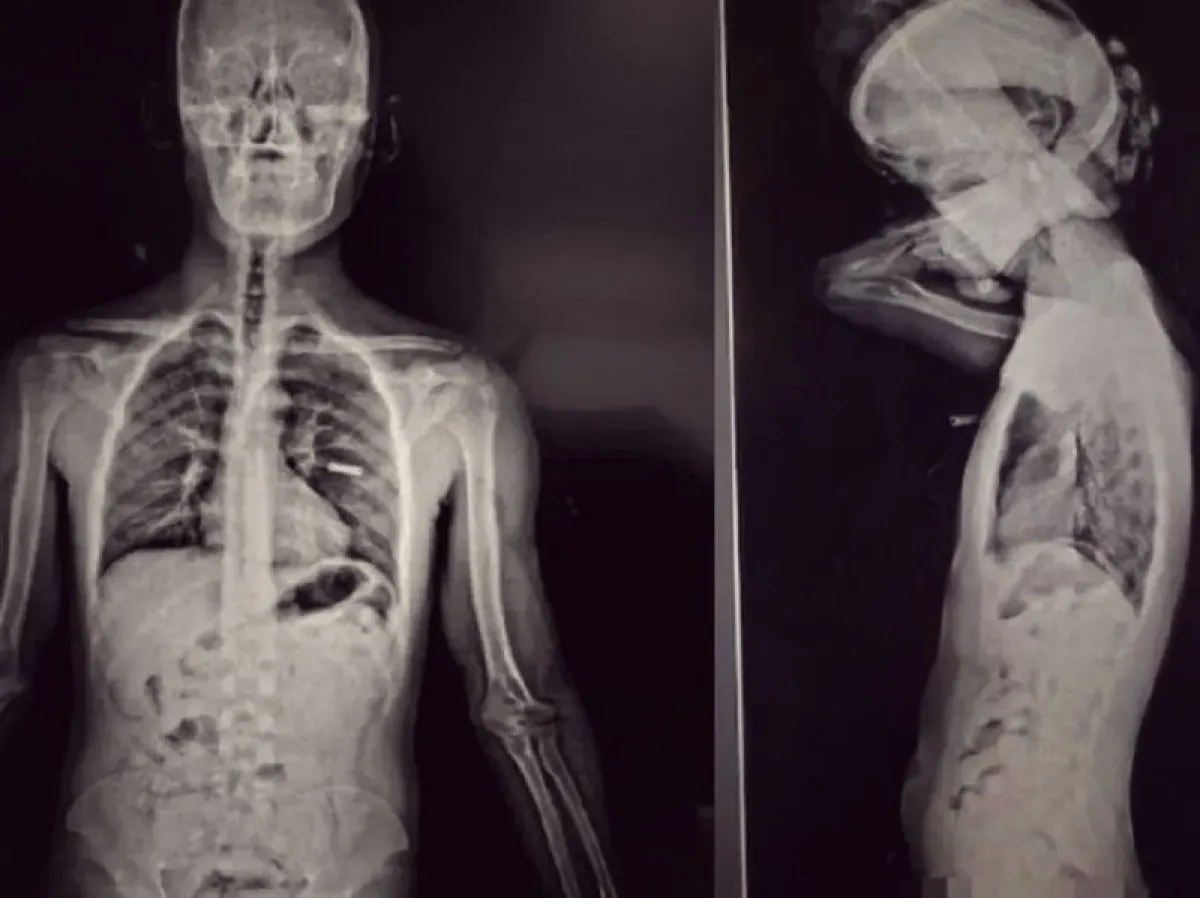

Los pasajeros fueron trasladados al Puente Internacional Horacio Guzmán, donde se les realizó un escáner corporal que detectó cuerpos extraños en la zona abdominal. Aunque ambos negaron haber ingerido cápsulas, se dio intervención a la Unidad Fiscal Federal de Jujuy. Los sospechosos fueron internados bajo custodia en el Hospital Dr. Jorge Uro de La Quiaca, donde los estudios radiológicos confirmaron la presencia de los elementos en sus organismos.

Horas después, los involucrados evacuaron un total de 192 cápsulas —96 cada uno— que contenían cocaína. El peso total de la droga fue de 2.218 gramos, equivalente a más de un kilo transportado por cada persona. Las pruebas químicas confirmaron la sustancia ilícita y el valor estimado supera los 47 millones de pesos.